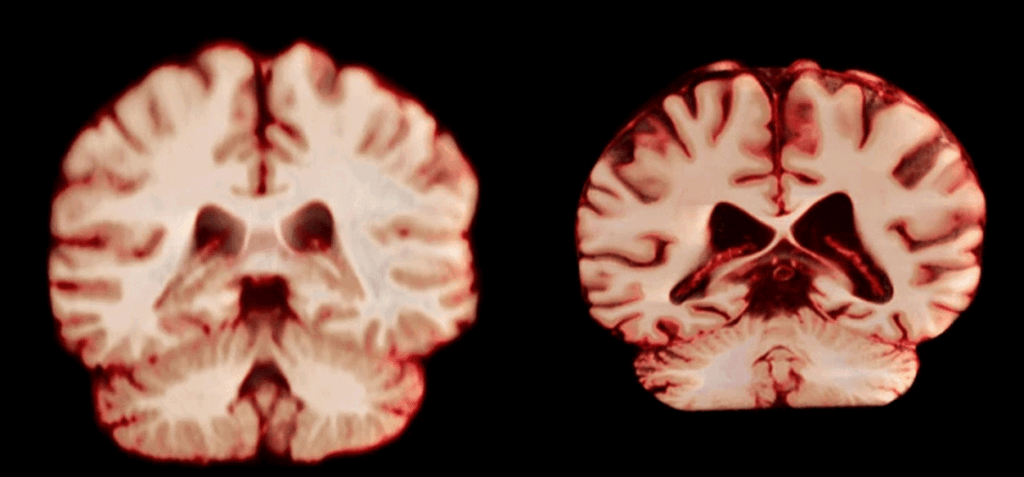

La ciencia confirma: el cerebro de los hombres envejece más rápido – Un nuevo estudio sobre las implicaciones que las diferencias de género en el envejecimiento cerebral tienen en el alzhéimer revela que los hombres experimentan una mayor reducción de volumen en más regiones del cerebro que las mujeres, recoge la revista Nature.

Durante la investigación se reunieron más de 12.500 escáneres cerebrales de participantes de entre 17 y 95 años, recopilados a lo largo de los años. Cada individuo se sometió al menos a dos resonancias magnéticas cerebrales, con un intervalo medio de aproximadamente tres años entre ellas.

Tras examinar las diferencias de tamaño cerebral basadas en el sexo, el equipo descubrió que los hombres mostraban un deterioro en un mayor número de regiones cerebrales, incluidas muchas partes de la corteza, a edades más avanzadas.